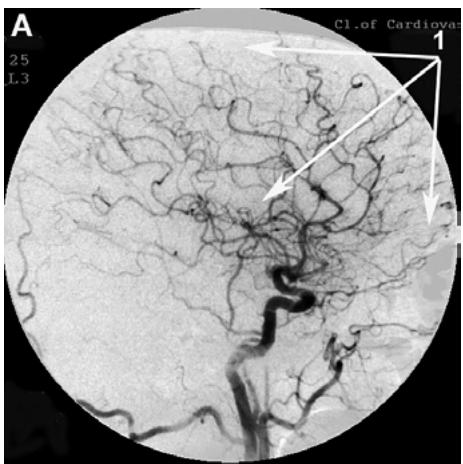

After transcatheter intracerebral laser PBMT, according to digital MUGA, all 48 (100%) patients showed a direct positive result manifested in pronounced angiogenesis, collateral and capillary revascularization, reduction of arteriovenous shunts, as well as an improvement in venous outflow (Figures 1A, 1B, Figures 2A, 2B).

Figure 1: Patient S., 42 years old, male. Medical history of AD - 2 years, TDR-1.

A. Left internal carotid artery angiogram, arterial phase, before transcatheter Intracerebral laser PBMT: 1. hypovascular areas in temporal and frontoparietal regions. B. Left internal carotid artery angiogram, arterial phase, after transcatheter intracerebral laser PBMT: 2. stimulation of angiogenesis, restoration of collateral and capillary blood supply in the temporal and frontoparietal region.